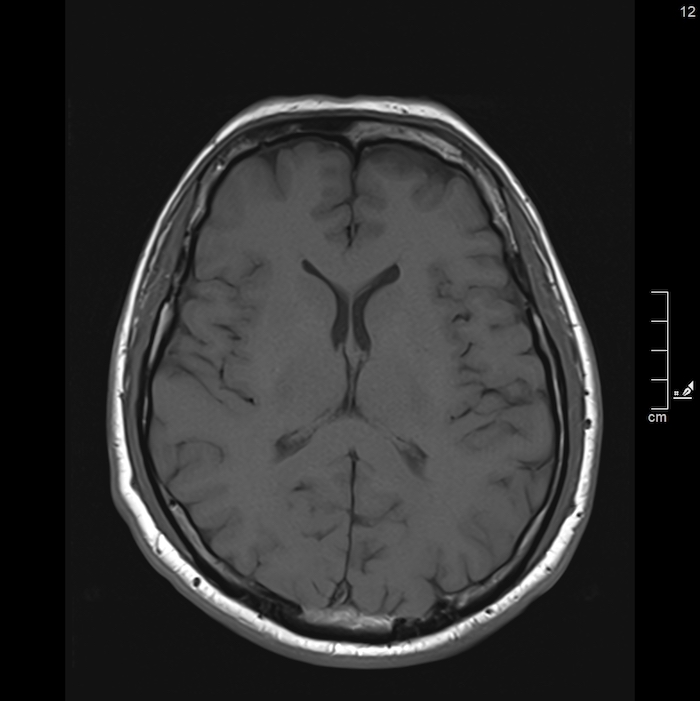

L’osservatore che accede a questo disco si trova davanti a un’estensione algoritmica, dove la biografia clinica del soggetto è scomposta in una serie di sezioni assiali, coronali e sagittali: una stratificazione ipertestuale che permette di navigare all’interno della carne. Si vede qualcosa che rivela la vulnerabilità e la complessità della nostra struttura biologica, trasformando l’intimità organica in un riflesso esterno, condivisibile e consultabile. La grana di queste immagini è la traccia concreta di un’interazione tra la téchne e il vivente, dove il contrasto tra i bianchi e i neri definisce i confini di un’identità che non risiede più soltanto nella psiche, ma nella capacità della macchina di rendere navigabile l’invisibile.

MZ: Nella tua pratica quotidiana, sezioni il corpo umano attraverso la risonanza magnetica per scopi diagnostici. In quale momento la “fetta” anatomica smette di essere un dato clinico per trasformarsi, ai tuoi occhi, in un reperto che può essere riletto secondo connotazioni concettuali o estetiche?

DS: Esiste un’estetica delle immagini per il medico? Sì. Si tratta tuttavia di un’estetica “morale”, vale a dire intimamente connessa allo scopo dell’immagine, la rappresentazione di quella parte di corpo umano che mi accingo a valutare. Ancora direi che nel caso della risonanza magnetica (ma vale per qualsiasi metodica di diagnostica per immagini), ci si confronta con un’immagine attesa, quella data dalla memoria di tutte le immagini “normali”, cioè sane, accumulate nella mente con l’esperienza. Il “sano” è una perfezione attesa, tuttavia non geometrica, non ideale, fondata piuttosto sulla memoria delle immagini corrispondenti ad una “perfezione biologica”. Esiste comunque uno stupore per la qualità delle immagini, legato al dettaglio anatomico (“sembra una sezione anatomica” è una delle frasi più ricorrenti) o alla maggior evidenza delle anomalie (frutto di una maggior risoluzione di contrasto).